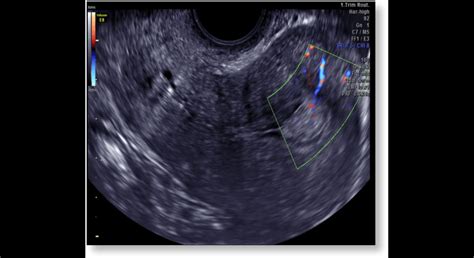

Ultrazvukové Vyšetrenie

Ultrazvukové vyšetrenie môže pomôcť zistiť, či sú v maternici nejaké abnormality, ako napríklad polypy alebo myómy, ktoré by mohli ovplyvniť menštruačný cyklus. Môže tiež pomôcť vylúčiť iné príčiny absencie menštruácie, ako napríklad tehotenstvo mimo maternice.

- Zvážte ultrazvukové vyšetrenie: Ultrazvukové vyšetrenie môže pomôcť vylúčiť iné príčiny absencie menštruácie, ako napríklad tehotenstvo mimo maternice alebo abnormality v maternici.